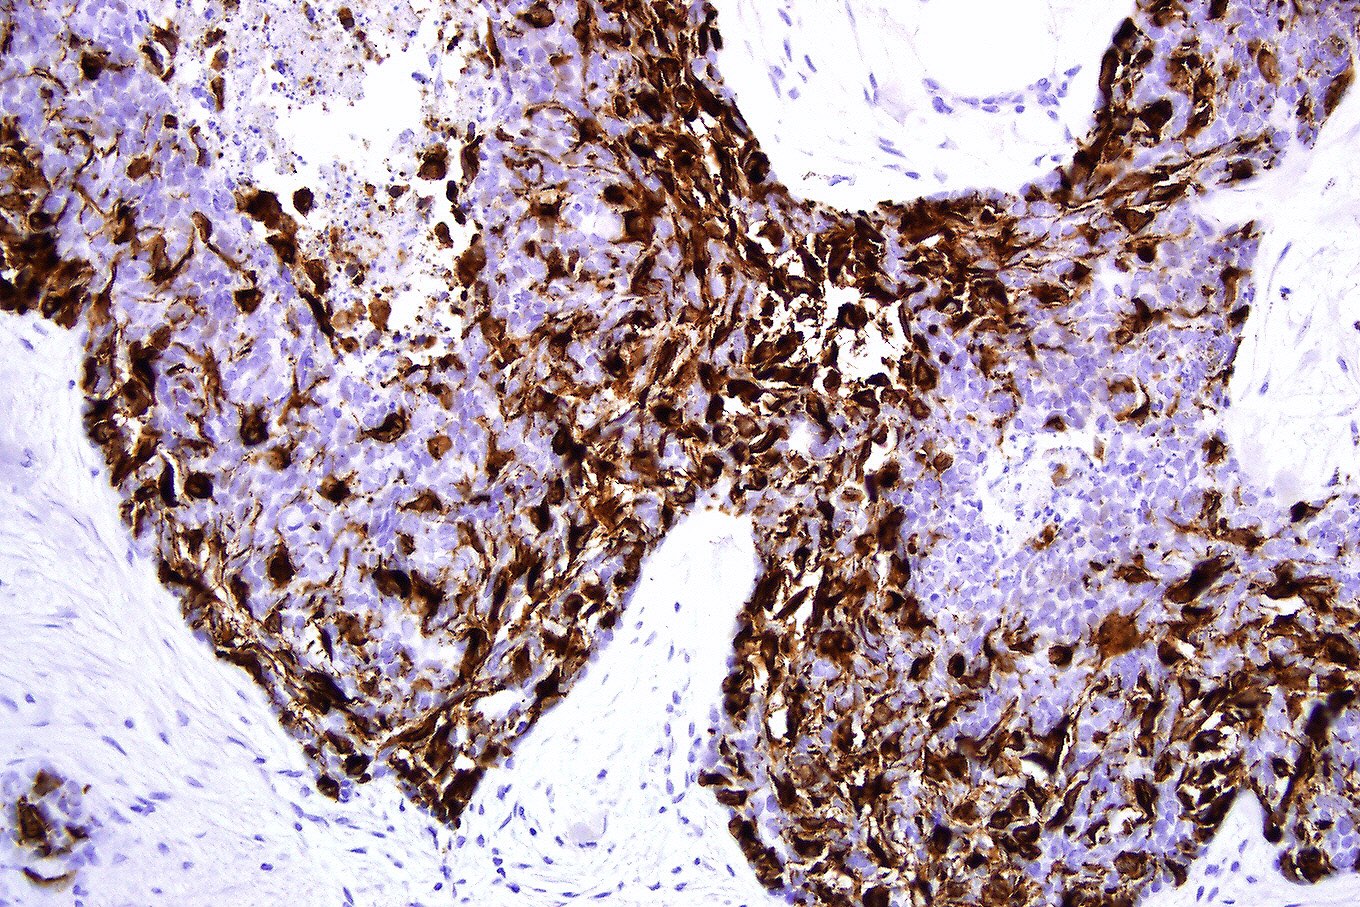

- Morpheaform (sclerosing, morphoeic) BCC

- Thin strands and nests of basaloid cells

- Limited peripheral palisading

- Stroma is dense and sclerotic

- Extensive spread

- Perineural invasion can be seen

Positive stains

- CK AE1 / AE3 (100%), BerEP4 (80 - 100%), p63 (100%), CAM 5.2 (20 - 95%), androgen receptor (33 - 66%), p53 (74.5 - 83%), 34 beta E12 (high molecular weight CK), BCL2 (diffuse pattern), CD10 (positive in tumor cells, negative in stroma) (Dermatopathology (Basel) 2015;2:15, Arch Pathol Lab Med 2017;141:1490, Rom J Morphol Embryol 2018;59:1115, Am J Pathol 1992;141:25)

Microscopic (histologic) images

Contributed by Antonina Kalmykova, M.D., Phillip H. McKee, M.D., Sate Hamza, M.D., Eduardo Calonje, M.D.,

Wayne Grayson, M.B.Ch.B., Ph.D., James Sampson, M.B.B.S., M.Sc. and Assia Bassarova, M.D., Ph.D.